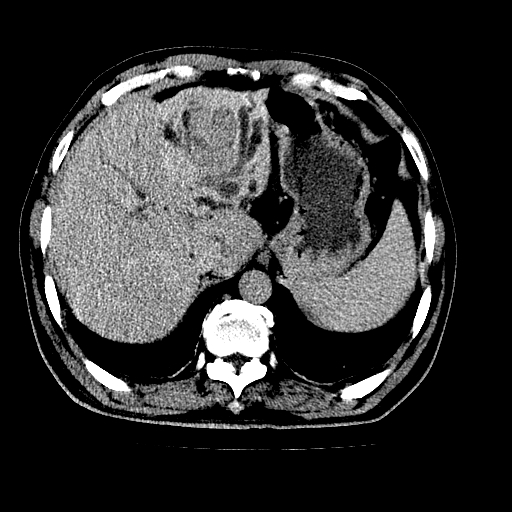

男,66岁,上腹部不适、黄染一周。彩超示:肝左叶占位,肝内胆管扩张,胆总管扩张,胆总管占位?

肝左叶不规则软组织肿块影,边缘不规整邻近肝实质受累分界不清;肝内胆管(左叶)明显扩张成“软藤状”,诊断:肝左叶胆管细胞癌。

肝左叶占位性病变,并胆管扩张,符合胆管细胞癌ct表现,门脉左支受累,左肾囊肿。窗宽太窄了,其他的看不清

左叶胆管细胞癌累及胆总管,门脉左支受侵,慢性胆囊炎胆结石,左肾小囊肿

肝左叶不规则软组织肿块影,边缘不规整邻近肝实质受累分界不清;肝内胆管(左叶)明显扩张成“软藤状”,诊断:肝左叶胆管细胞癌。胆囊钙乳症。